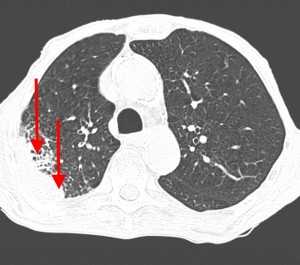

Вторичные узлы гематогенного характера чаще всего имеют ровные края, четкие контуры и однородную структуру. Возможны изменения структуры опухоли вследствие кровоизлияния в паренхиму, обызвествлений, некроза центральной части узла, а также рубцов. Края узла могут стать нечеткими, расплывчатыми, если опухоль провоцирует отек легочной паренхимы, либо «лучистыми», если имеет место опухолевый лимфангиит.

Чаще всего метастазы выглядят как множественные очаги. Одиночные вторичные узлы крайне редки и встречаются меньше чем в 5% случаев. Чем больше узлов выявлено, тем выше вероятность их метастатической природы. Одиночный метастаз нужно дифференцировать с первичным раком, для этого обычно требуется тканевое исследование после оперативного вмешательства или биопсии.